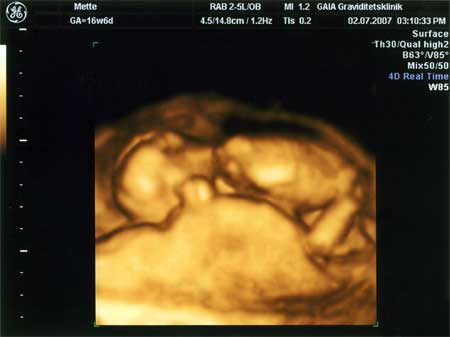

3D scanning – se baby i maven under graviditeten

3d scanning uge 16

3d scanning – uge 16

uge 16+0

Jeg ligger og putter mig op ad "madpakken"